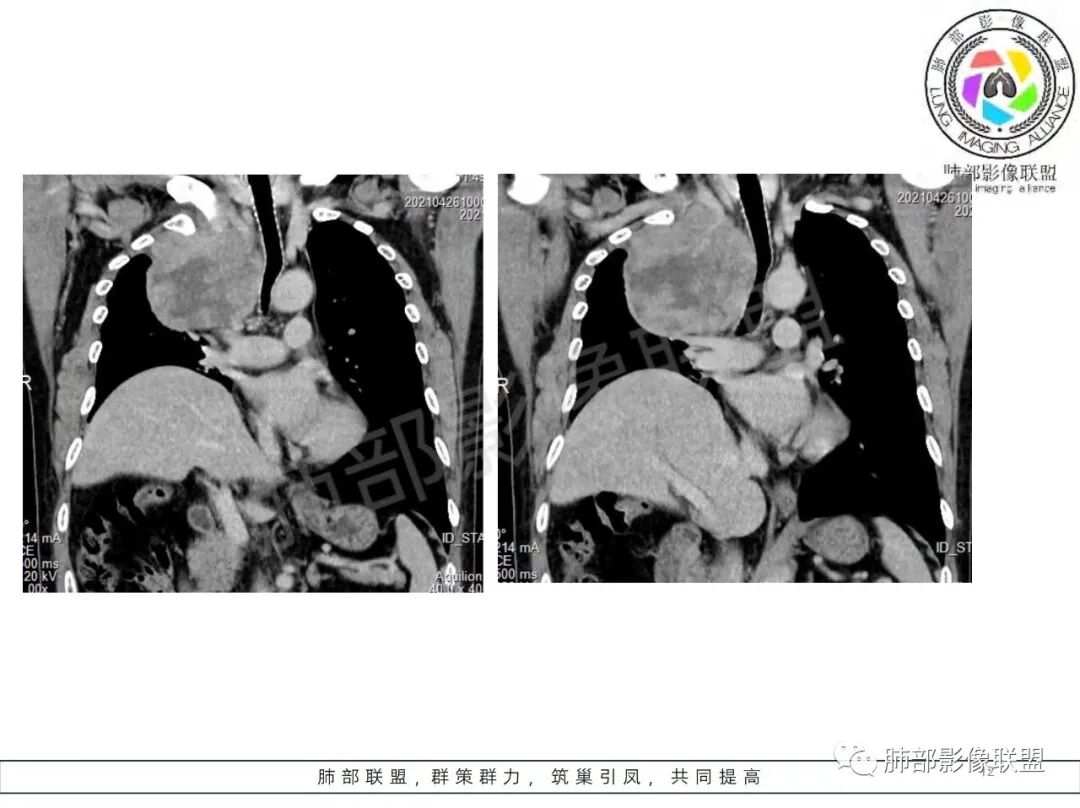

定位肺外,来源于胸膜的SFT(蛇纹状血管)、鞘瘤(不均匀强化,囊变坏死多)、间质瘤(部分层面与食管分界不清)。

男,69岁,间断咳嗽4个月,右上肺体积缩小,可见巨大软组织占位,胸膜掀起,考虑来源于肺外,平扫密度不均匀,增强扫描明显不均匀强化,内部可见粗大血管及坏死区,周围组织受压移位。局部与食管分界不清,穿刺提示短梭形细胞,来源于间叶组织可能,综合考虑为神经鞘瘤>SFT

肿块把上腔静脉向前部推移,对肺内血管以及气管以推移为主,占位未见肺部血管供血,胸膜掀起处胸膜下脂肪间隙增宽,说明定位在肺外 SFT多为脏层胸膜起源,少部分壁层胸膜起源,壁层胸膜起源SFT不除外,但是胸膜掀起处胸膜下脂肪间隙增宽了,感觉SFT可能性比较小,这样囊变 AB区 纵膈神经起源的神经鞘瘤需要重点考虑,因为CT给的层不够,看不到肿瘤与椎间孔的关系,不敢确定,曾经病理提示高度考虑叶间起源肿瘤,肿瘤细胞呈短梭形细胞构成 不知道和神经鞘瘤是否符合!我重点考虑神经鞘瘤

粗大强化血管,主要看他起源,如果是来源肺动脉,肺内血管供血一是肺内二是脏层胸膜,肺内排除,只剩脏层胸膜SFT;如果这个是纵隔供血,那它可能是神经源性或者壁层胸膜,也可以是SFT比较少

好发于肺胸壁交界区或纵隔交界区,病灶部位对病灶性质判断有较大价值。多单发,有包膜,边界清。

密度:与肿瘤细胞疏松或密集、胶原纤维含量、出血、坏死、囊变及黏液变性等有关。镜下由梭形细胞组成、细胞间由胶原纤维沉积,CT平扫肿瘤实性部分为等、稍低密度,胶原纤维易发生黏液变性或囊变,呈多发灶性或不规则星芒状低密度区,较少出现钙化。一般肿瘤小,密度多均匀,肿瘤大,多发生坏死、囊变,密度多不均匀,。

强化方式:多均匀或不均匀明显强化,增强肿瘤内可见迂曲血管影(蛇纹血管等),肿瘤较大可见“地图样”强化。

恶性倾向:体积较大,多见出血、囊变及坏死;强化多不均匀;呈浸润性生长,与周围组织器官边界不清;出现远处转移等。